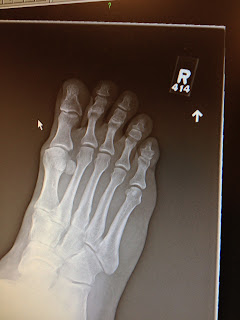

Bill's deformed foot

So Bill's big toe never grew properly and his foot has tried to make up for it. He went to see an orthopedic doctor today and was told he need to wear orthopedic inserts for the swelling and terrible foot pain he's been having. Well, at least now he knows why his foot was hurting him.